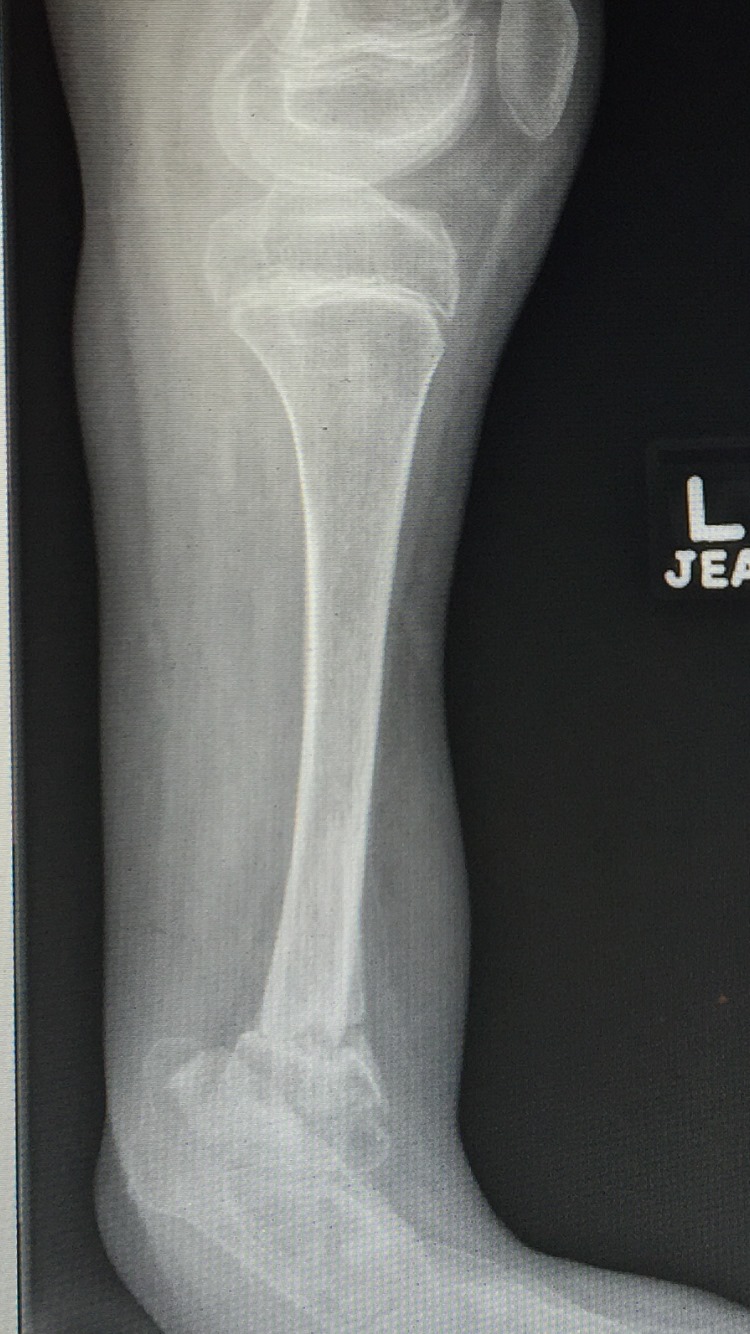

Ausencia congenita del peroné

A los papás de Lazarito les dijeron en Estados Unidos que la única alternativa para su hijo era una amputación; buscando segundas opiniones, llegaron conmigo. Lazarito, de 13 años, tiene #hemimelia #perónea, una ausencia congénita del peroné que causa malformaciones y acortamientos. Para evitar la amputación, se le realizó una reconstrucción del tobillo y alineamos su pierna de forma funcional. Ahora, mi pacientito ya camina con apoyo al 100%, realiza sus actividades diarias y dice que empezará a jugar fútbol. Agradezco a sus papás por la confianza y a sus familiares en Guadalajara por recomendarlo conmigo.